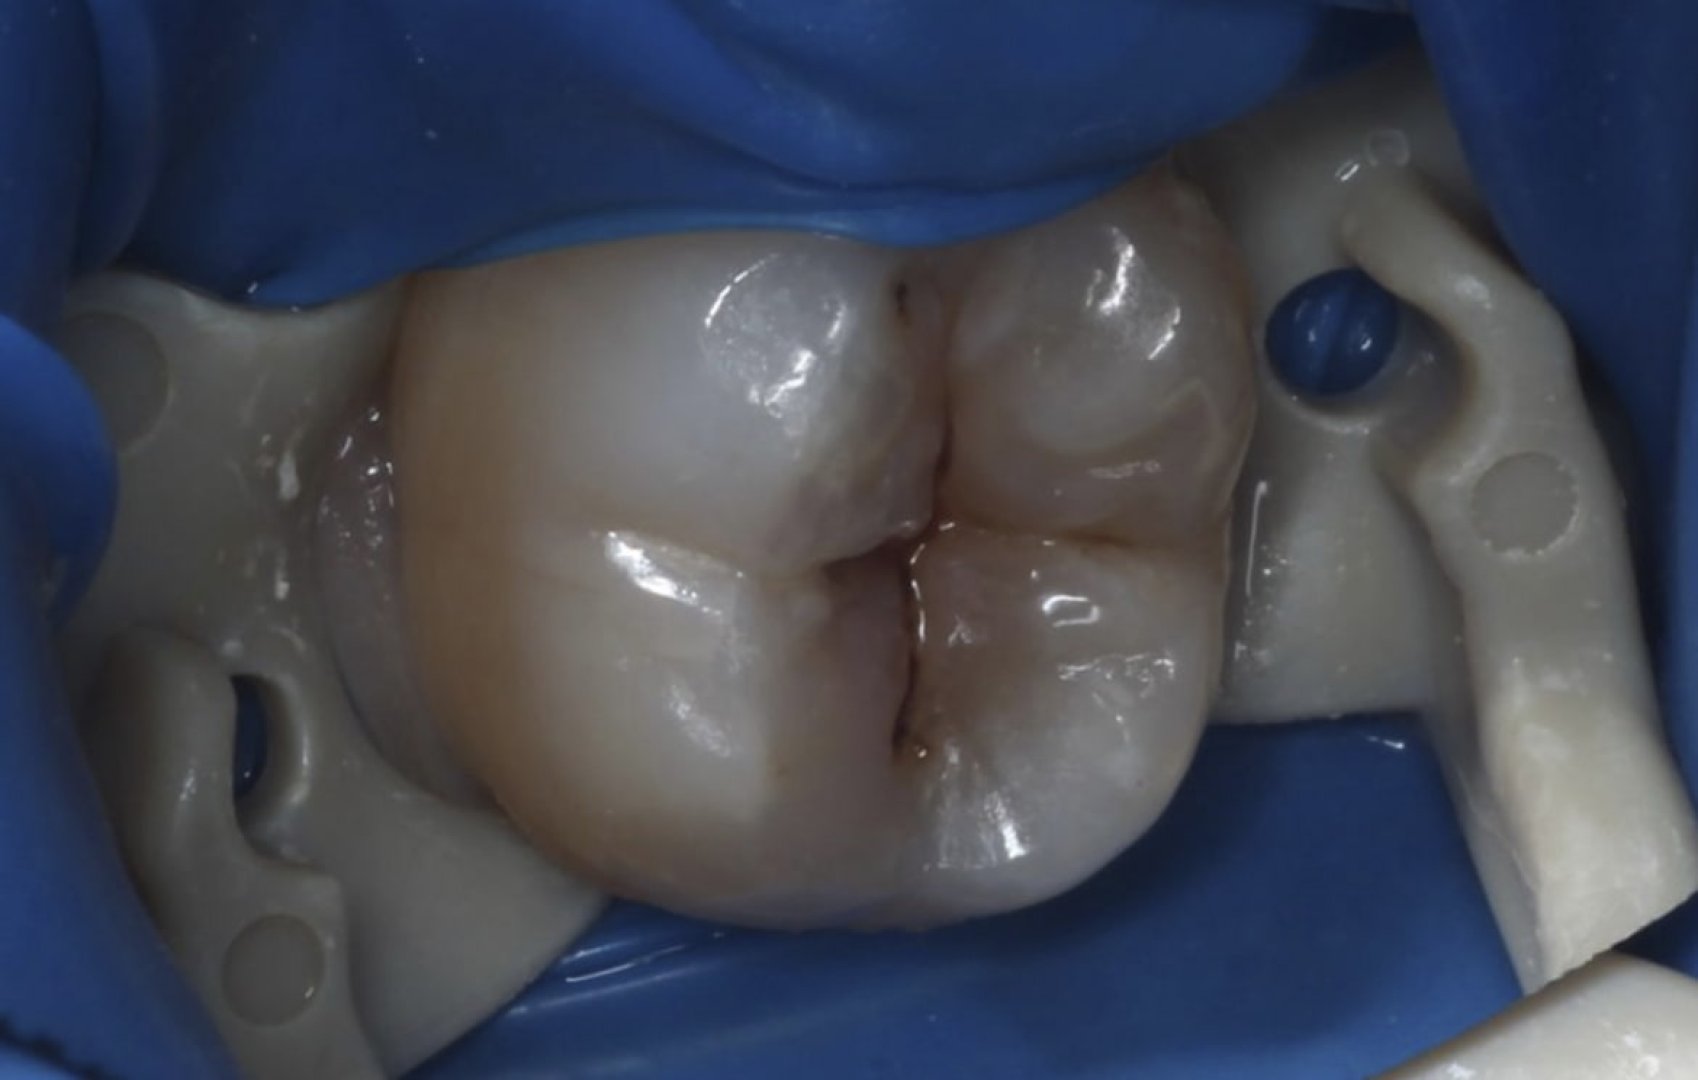

История пациента

Жалобы на боль при накусывании и потемнение эмали одного зуба. Цель — сохранить ткани и вернуть естественную эстетику.

Этапы лечения

Микроскопная диагностика; изоляция коффердамом; щадящее удаление кариеса; послойная художественная реставрация композитом с точным подбором оттенка; формирование контактных пунктов; финишная полировка.

Результат

Герметичность и анатомия восстановлены, переходы незаметны.

ДО

До лечения кариеса и реставрации

ПОСЛЕ

После реставрации под микроскопом